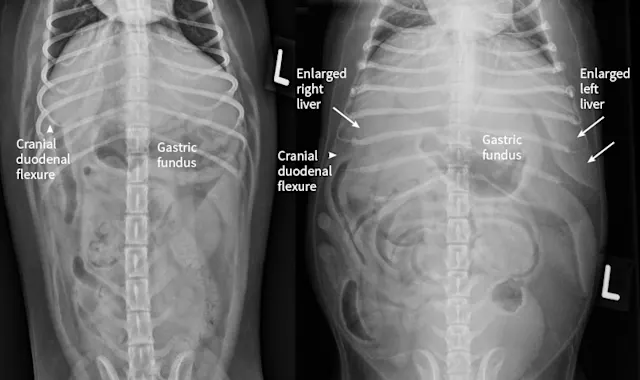

Right lateral radiographs of a clinically normal dog (A) and an 11-year-old neutered male dachshund with diabetes mellitus (B). The dog with diabetes mellitus has a pendulous abdomen and an enlarged liver (ie, hepatomegaly) with rounded margins that extend caudal to the costal arch (B; arrows). The gastric axis (solid lines; aligned with the gastric fundus dorsally to the antrum ventrally) is parallel to the ribs in the clinically normal dog but caudally displaced in the dog with hepatomegaly. Common differential diagnoses for generalized hepatomegaly are vacuolar hepatopathy due to endocrinopathies or other metabolic disease (eg, lipidosis), infectious and noninfectious inflammatory disease, neoplasia, storage disease, and venous congestion.